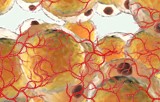

Adipose tissue is a loose connective tissue composed mainly of lipid-rich cells called adipocytes. In addition to adipocytes, adipose tissue contains the stromal vascular fraction (SVF) of cells including preadipocytes, fibroblasts, vascular endothelial cells and a variety of immune cells such as macrophages. There are 2 types of adipose tissue: white adipose tissue (mainly in adults) and grey adipose tissue (mainly in newborns). Adipose tissue is mainly located under the skin but can also be found as deposits in the muscles and intestines.

The fat cell system stores energy, acts as an endocrine organ, insulates and protects the body. Abnormal proliferation and regulation of cells within the adipose system contribute to the development of disorders such as obesity and cardiovascular disease.

We propose different types of adipose tissue cells: adipocytes, adipose tissue-derived stem cells, pre-adipocytes and microvascular endothelial cells.